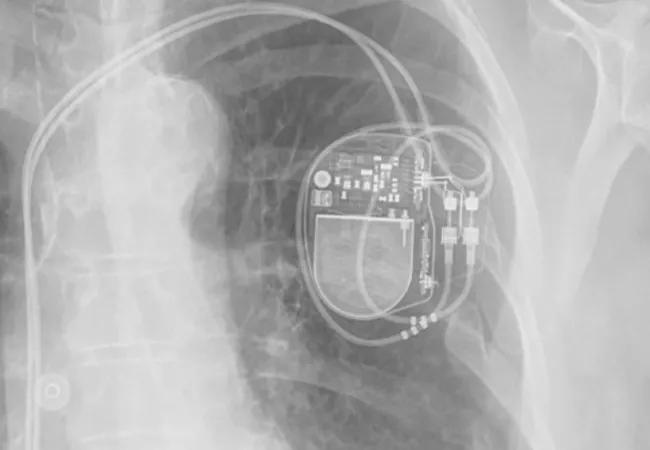

X-ray showing a dual-chamber pacemaker

Image credit: Cleveland Clinic Journal of Medicine